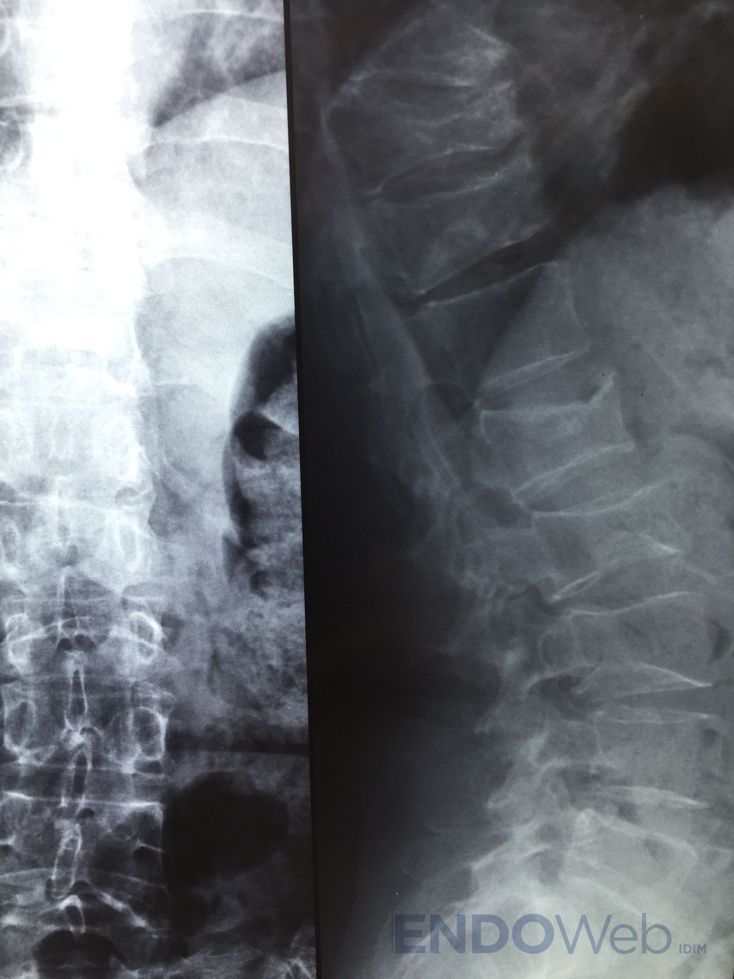

Se solicitó radiografía de columna dorso-lumbar:

Disminución altura vertebral cuerpos vertebras dorsales: D5, D8, D10 y D11. Biconcavidad vértebras lumbares L1 L2 L3